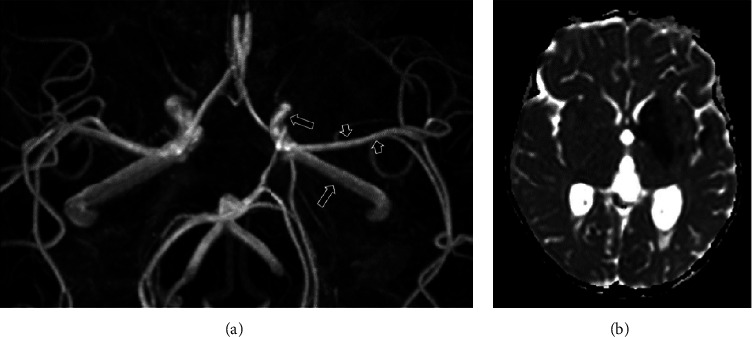

Abstract Image